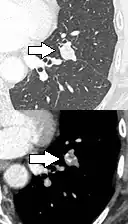

- Margin morphology: a spiculated margin is a risk factor for cancer.[8] Benign causes tend to have a well defined border, whereas lobulated lesions or those with an irregular margin extending into the neighbouring tissue tend to be malignant.[10] In particular, spiculations are highly predictive of malignancy with a positive predictive value up to 90%.[9] Also, a "notch sign", which is an abrupt indentation of the nodule, increases the risk of cancer, but may also be found in granulomatous diseases.[9]

subpleural nodule.[9]

Round well-delineated solid lung nodule with smooth border.[9]

Lobulated nodule.[9]

Spiculated lung nodule.[9]

A "notch sign".[9]

A triangular perifissural node can be diagnosed as a benign lymph node.[9]